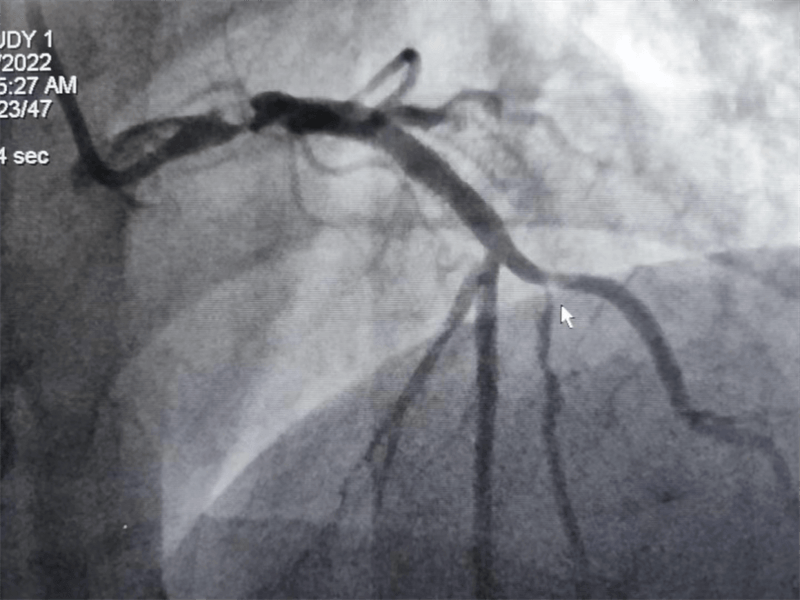

我們結(jié)合患者病變特點(diǎn),對(duì)回旋支支架內(nèi)閉塞病變處藥物球囊治療,左主干病變植入1枚支架,術(shù)后,造影顯示左主干病變處支架植入狀態(tài)良好,血管內(nèi)超聲顯示支架貼壁良好,患者血壓、心率穩(wěn)定,癥狀完全緩解,并安全返回重癥監(jiān)護(hù)室進(jìn)一步治療,術(shù)后張大伯無(wú)明顯不適,生命體征穩(wěn)定,病情明顯好轉(zhuǎn)。